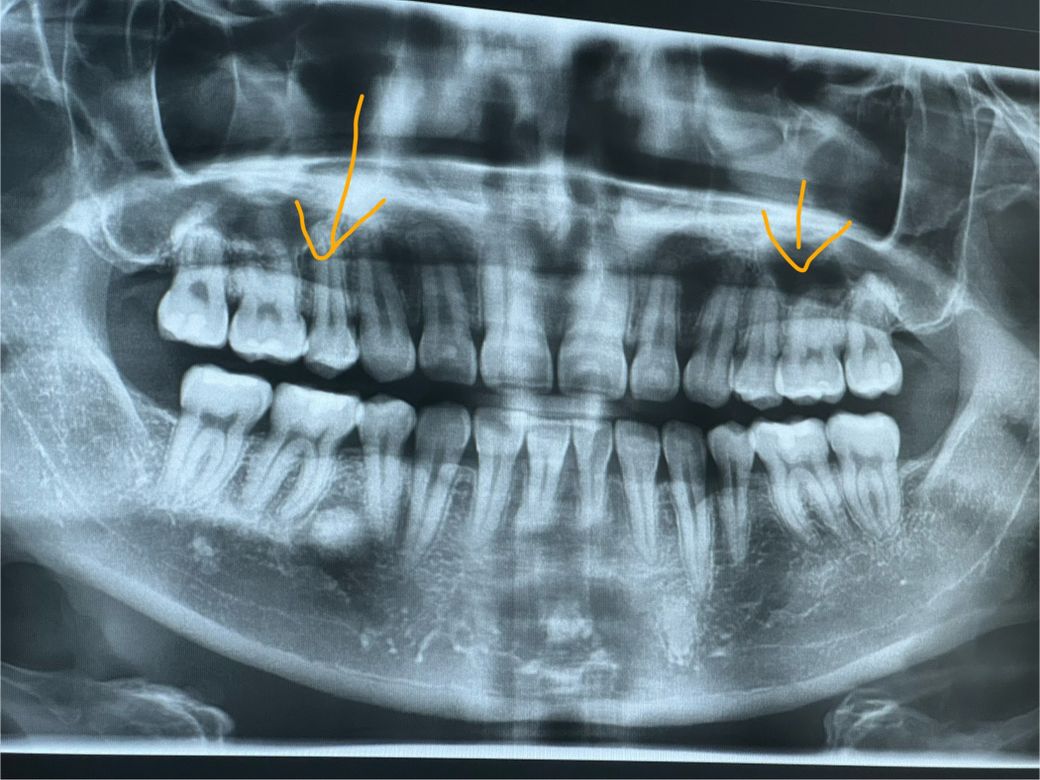

통증 없고 오래된 윗니 인접면 충치입니다. 엑스레이 봐주세요.

통증은 없고 인접면 충치가 2개가 있는데 생긴지는 좀 오래됐습니다. 치료하려면 세라믹 인레이로 4개 치아 비용이 들어간다고 하네요.

엑스레이로 봤을 때는 어디가 충치 부위인지 모르겠는데 사진으로 보이시나요? 개인적인 의심 부위는 제가 주황색으로 표시해놨어요.

파노라마 사진으로는 인접면 충치를 정확히 보기는 어렵고 작은 사진을 찍어봐야 알수 있습니다. 작은 어금니쪽에 충치가 잇는것처럼 보이긴합니다. 요즘은 금으로 하지 않고 치아색나는 재료로 많이 합니다.

파노라마는 개별 치아의 진단이 쉽지 않고 육안 사진 혹은 치근단 사진이 필요합니다.

오른쪽 위에 제이소구치 뒤쪽으로는 방사선상으로 충치가 보입니다 하지만 다른 부위에는 치아가 겹쳐져 있어서 정확히 보이지 않습니다 충치의 여부를 정확히 확인하기 위해서는 육안으로 확인을 하는 것이 중요할 것으로 생각됩니다.